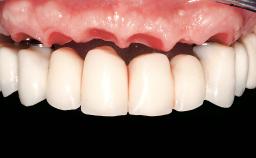

Immediate Loading of Four Implants in the Mandible and Six Implants in the Maxilla and Final Restoration with a Full-Arch Metal Framework FDP and a Full-Arch CAD/CAM Zirconia Framework FDP

A 65-year-old female patient with a failing residual maxillary dentition and a complete mandibular removable denture was referred for consultation and treatment. The patient’s chief complaint was that her upper residual teeth were mobile and she was unable to chew. The patient also asked us to improve the esthetic appearance of her smile. The patient’s desire was a stable and comfortable dentition in both jaws, and she specifically asked for a fixed rehabilitation. The patient reported a history of recurrent caries, endodontic complications, and periodontal disease as main reasons for previous teeth extractions. The anamnesis was negative for bruxism and TMJ disorders. The patient had no systemic diseases, was not on any medication,and did not smoke. The extraoral examination revealed a medium lip line, a wide diastema between the two central incisors (which, according to the patient, had appeared recently), and a partial collapse of the perioral soft tissues, probably due to loss of the correct vertical dimensions.

Prosthesis Type FDP